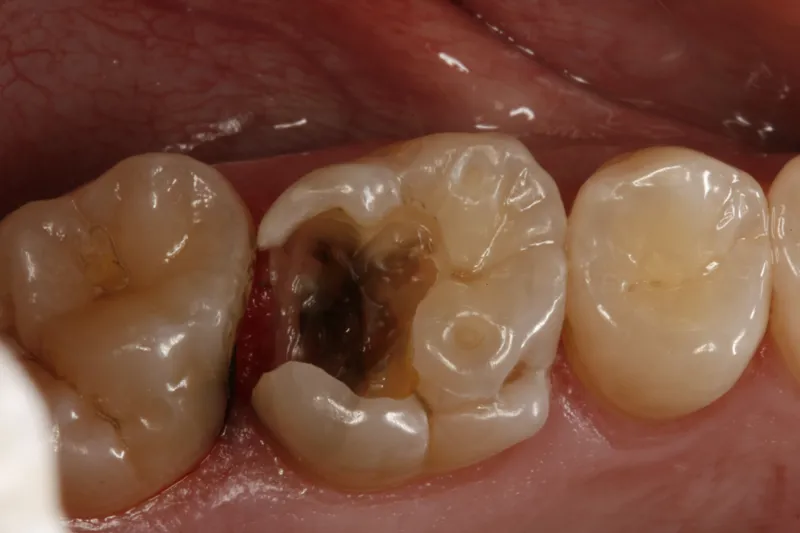

Stort cariesangreb på en kindtand